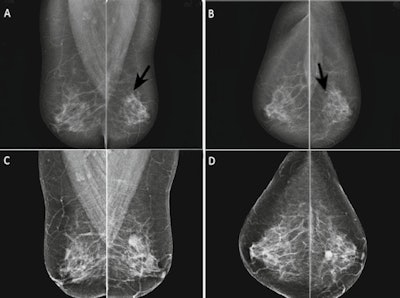

When transitioning from film-screen mammography (FSM) to full-field digital mammography (FFDM), going digital increases the number of repeated recalls for the same mammographic abnormality, found a large Dutch study published on 14 May in European Radiology.

The research group compared screening outcomes in women recalled twice for the same mammographic lesion before, during, and after the transition from FSM to FFDM, finding more women were repeatedly recalled during and after the transition to FFDM. The cancer risks were comparable before and after the transition, according to lead author Dr. Rob van Bommel from the radiology department at Catharina Hospital in Eindhoven, the Netherlands.

Previous research has shown the transition to full-field digital mammography increased the breast cancer detection rate, especially of low- and intermediate-grade ductal carcinoma in situ (DCIS) and lower-grade invasive cancers. The increased cancer detection rates are usually accompanied by higher recall rates and lower PPV of screening mammography at FFDM than at FSM, the authors explained.

More women experienced a repeated recall for the same mammographic lesion during the transition from FSM to FFDM screening, and the phenomenon persisted after the transition, the study authors wrote. The increased chance of a repeated recall came along with a nonsignificantly decreased PPV of recall. Also, cancers diagnosed after a repeated recall showed a more favorable tumor stage and grading than interval cancers.